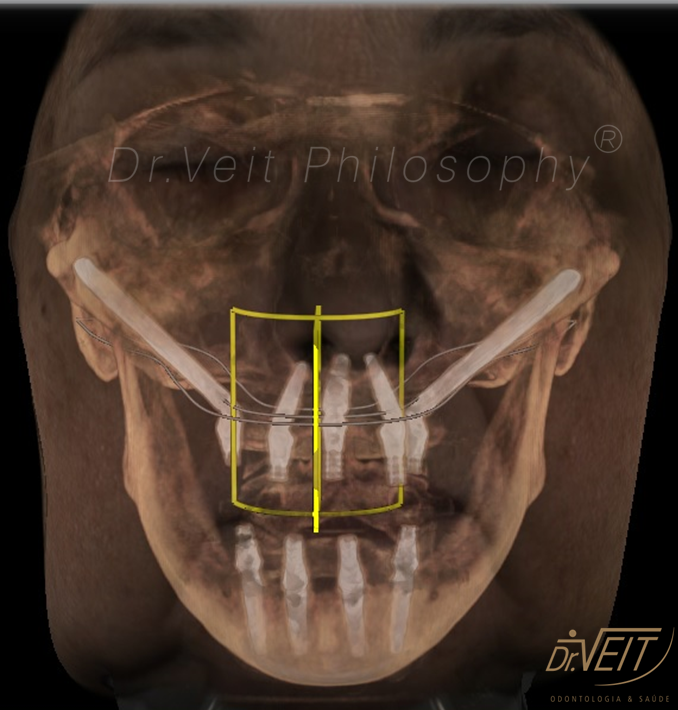

Arte de reabilitar os casos “impossíveis”. Pacientes que buscam a reabilitação oral podem conquistar um belo sorriso com segurança, mais conforto e tranquilidade com o uso do Implante Zigomático. A técnica possui o diferencial de realizar a implantação no osso zigomático e é indicada para casos de perda óssea maxilar avançada.